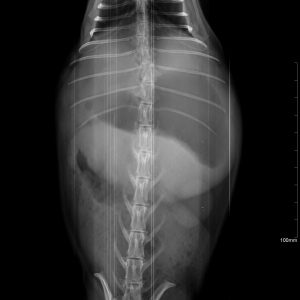

El diagnóstico por imagen es una herramienta fundamental en la medicina veterinaria moderna, ya que permite evaluar de forma precisa y no invasiva las estructuras internas del paciente. A través de técnicas avanzadas como la radiografía digital y la ecografía, es posible identificar alteraciones anatómicas y funcionales que facilitan un diagnóstico temprano y un manejo clínico más eficaz.

Trabajamos en estrecha colaboración con veterinarios clínicos para asegurar una correcta correlación entre los hallazgos de imagen y la situación clínica del paciente, optimizando así el abordaje diagnóstico y el seguimiento evolutivo.